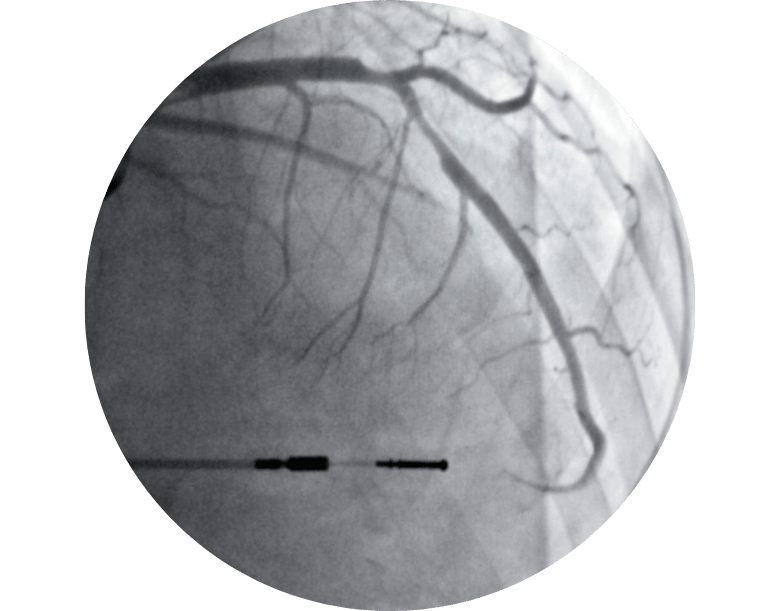

Anjiyografi: Tıkanıklık oranını belirlemek için

Girişimsel yöntemler: Anjiyoplasti, stent takılması veya bypass ameliyatı